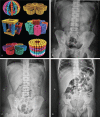

Magnetic foreign bodies ingestion is a special cause for attending emergency department. Here, we aim to analyze the characteristics and treatments of children who ingested magnetic foreign bodies (Buckyballs). Data were collected from children who ingested Buckyballs between February 2017 and October 2019. A retrospective analysis was performed to summarize the experiences of conservative treatment, gastroscopy and surgery when dealing with Buckyballs ingestion.A total of 49 patients with buckyballs ingestion were identified, of whom 11 underwent conservative treatments, 6 underwent gastroscopy, and 32 underwent surgery. Among such individuals, eight patients (72.7%) had a successful conservative treatment (number of Buckyballs [NB]: 3.5[IQR: 2.0-4.0]); four patients (66.7%) had Buckyballs successfully removed by gastroscopy (NB: 3.5[IQR: 3.0-5.5]); 16 asymptomatic (50%) patients (NB: 4.0[IQR: 3.0-8.0]) and 16 symptomatic (50%) patients (NB: 8.5 [IQR: 6.25-11.75]) received emergency surgery. Compared to patients who received conservative treatment, the number of ingested Buckyballs was significantly higher in patients who received surgery or gastroscopy (7.0 [IQR: 3.0-10.75] vs 3.5 [IQR: 2.0-4.0], P < .05). The risk of intestinal perforation was significantly higher in symptomatic patients (P < .05) compared to asymptomatic patients.Gastroscopy is recommended when Buckyballs are in the stomach or esophagus. In asymptomatic patients, conservative treatment can be considered for 4 to 6 days. Patients failing conservative treatment, or those who are symptomatic should undergo emergency surgery.